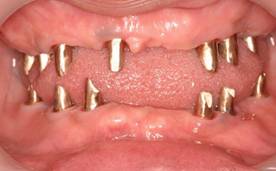

よく噛めなかったケース

術前。62歳男性。仮の歯の入っている上顎前歯部は抜歯するしかない状態。右下がない為右上臼歯が伸びだしていました。入れ歯では咬めないのでインプラントを希望され紹介されて来院されました。

63歳術後。よく噛めるようになり喜んでいただけました。

術前のパノラマレントゲン写真。仮歯を支えている4本の歯は根が残っているだけで抜歯の必要がありました。

63歳術後のパノラマレントゲン。インプラントはスプラインツイスト